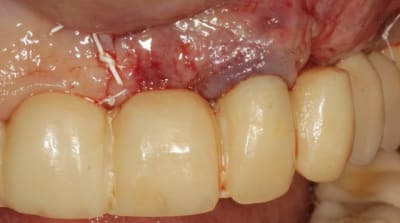

Grosse perte osseuse au niveau de la 23, ROG avec Bio-Oss et autogène dans un rapport 50/50, le tout recouvert pas une BIo-gide maintenu avec de pin's.

Désolé pour le retard, je vais essayé de répondre à tout le monde, mettre un implant et faire une ROG de façon predictible dans un cas comme ça c'est impossible, la photo pré-op c'est la dernière ( je ne sais pas pourquoi nonol m'a inversé l'ordre ), à noter que j'ai fait ce design d'incision car 24 et 25 sont des implants et je ne voulais justement pas me retrouver avec une récession.

J'ai utilisé du BIo-Oss et de l'autogène prélevé avec un scraper à la mandibule, le tout recouvert par une Bio-Gide maintenu par des pin's, suture avec du Gore Tex ( e-PTFE ) et du Cytoplast (PTFE )